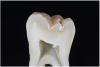

Often patients present for an examination with the clinical finding of an occlusal fissure similar to that shown in Figure 1, yet there is no clinically perceptible “stick” with an explorer. The clinician thus faces the decision of whether occlusal decay exists requiring a restoration or whether the lesion should merely be “watched” to determine if it progresses further. To make the correct decision, an understanding of the detection and classification of pit-and-fissure lesions is needed.

Fig 1. Clinical presentation with no detectable fissure to probing. Blue marks indicate occlusion.

Figure 1